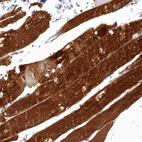

Immunohistochemical staining of human skeletal muscle shows strong cytoplasmic positivity in myocytes.